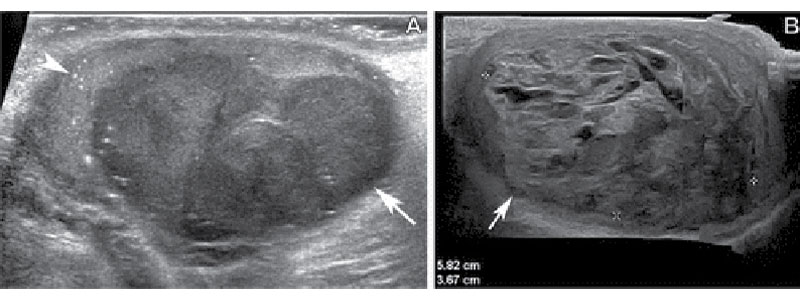

Differentiation of seminomas from nonseminomatous mixed germ cell tumors (NSGCTs). (A) Gray-scale US image of the scrotum in a 27-year-old man shows a well-circumscribed homogeneously hypoechoic testicular mass (arrow) with associated microlithiasis (arrowhead), which was proved to be a pure seminoma at pathologic examination. (B) Gray-scale US image of the scrotum in a 32-year-old man shows an ill-defined heterogeneously mixed echogenic mass (arrow) with scattered anechoic areas representing cystic or necrotic changes, which was proved to be an NSGCT composed of 45% postpubertal teratoma, 30% yolk sac tumor, 20% embryonal carcinoma, and 5% choriocarcinoma.

Katabathina et al, RadioGraphics 2021; 41:1698–1716 ©RSNA 2022